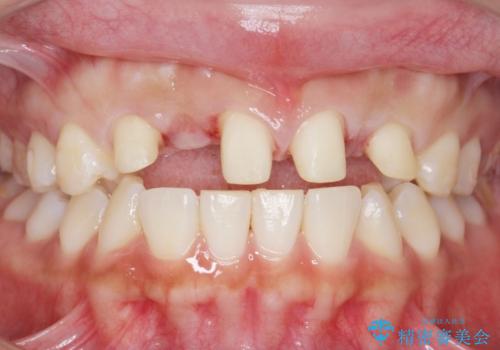

- 生まれつき上の側切歯と犬歯が逆に生えていることを主訴に来院された患者様です。

他院で矯正を行っていたそうですが、なかなか終わらないため途中で治療をやめてしまったとのことでした。

矯正以外の治療法で早く治したいとのご希望により、上顎両側犬歯を抜去しオールセラミックのブリッジによる補綴治療を行いました。